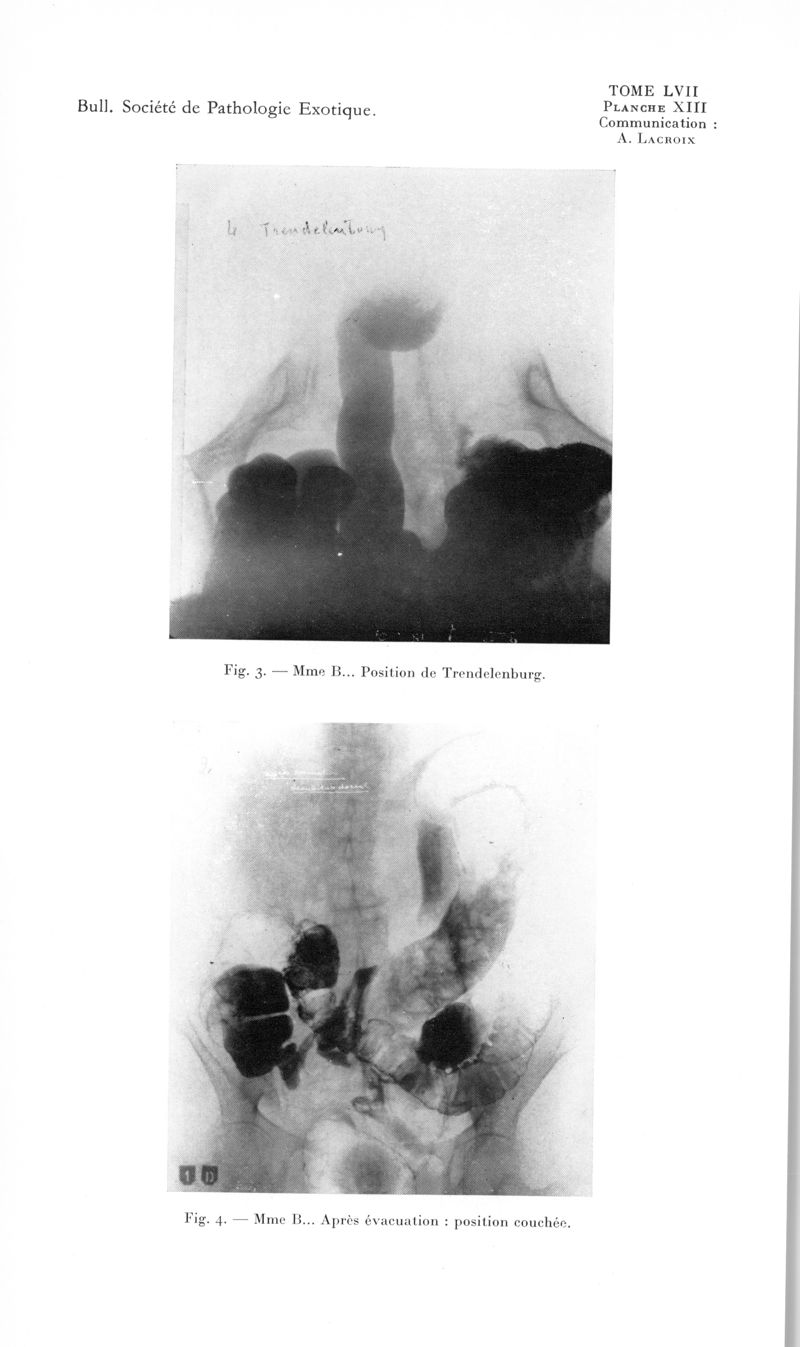

Bulletin de la Société de pathologie exotique et de ses filiales

1964, tome 57. - Paris : Masson, 1964.